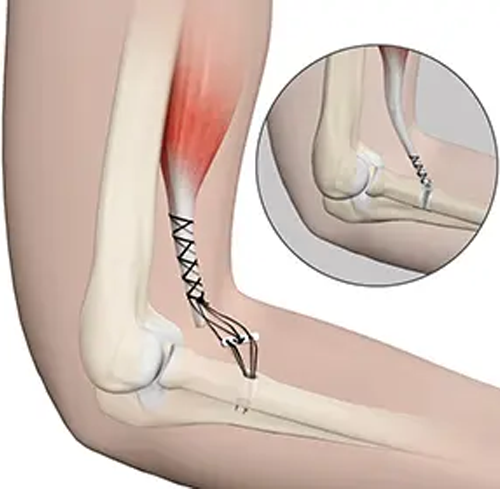

پارگی این تاندونها ممکن است بهصورت کامل یا جزئی رخ دهد و معمولاً در اثر فشار بیشازحد، ضربه مستقیم یا حرکات ناگهانی اتفاق میافتد. در صورتیکه پارگی کامل باشد، عملکرد طبیعی مفصل دچار اختلال جدی خواهد شد.

بیمار ممکن است نتواند بهدرستی بازوی خود را خم یا صاف کند. در موارد پارگی تاندون دوسر یا سهسر، کاهش قدرت عضلانی شدید دیده میشود.

۵. تغییر شکل ظاهری بازو

در موارد پارگی کامل، عضله جدا شده و به عقب جمع میشود که باعث ایجاد برجستگی غیرطبیعی یا گودی غیرعادی در بالای ساعد میشود.

پارگی تاندون آرنج یک آسیب جدی است که در صورت تشخیص دیرهنگام، میتواند عملکرد حرکتی و کیفیت زندگی را تحت تأثیر قرار دهد. شناخت علائم، تشخیص دقیق و اقدامات پیشگیرانه میتواند از آسیب دائمی جلوگیری کند. درمان بهموقع توسط متخصص ارتوپدی یا فیزیوتراپیست، کلید بازگشت سریع به فعالیتهای روزمره است. این درمان می تواند جراحی تاندون آرنج یا .. باشد.